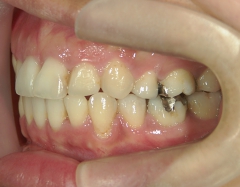

矯正歯科 治療後矯正歯科 全顎ワイヤー矯正 治療後矯正歯科(全顎ワイヤー矯正)治療後

矯正歯科 治療後

no.31_1962_治療後_右.JPGno.31_1962_治療後_正面.JPGno.31_1962_治療後_左.JPG